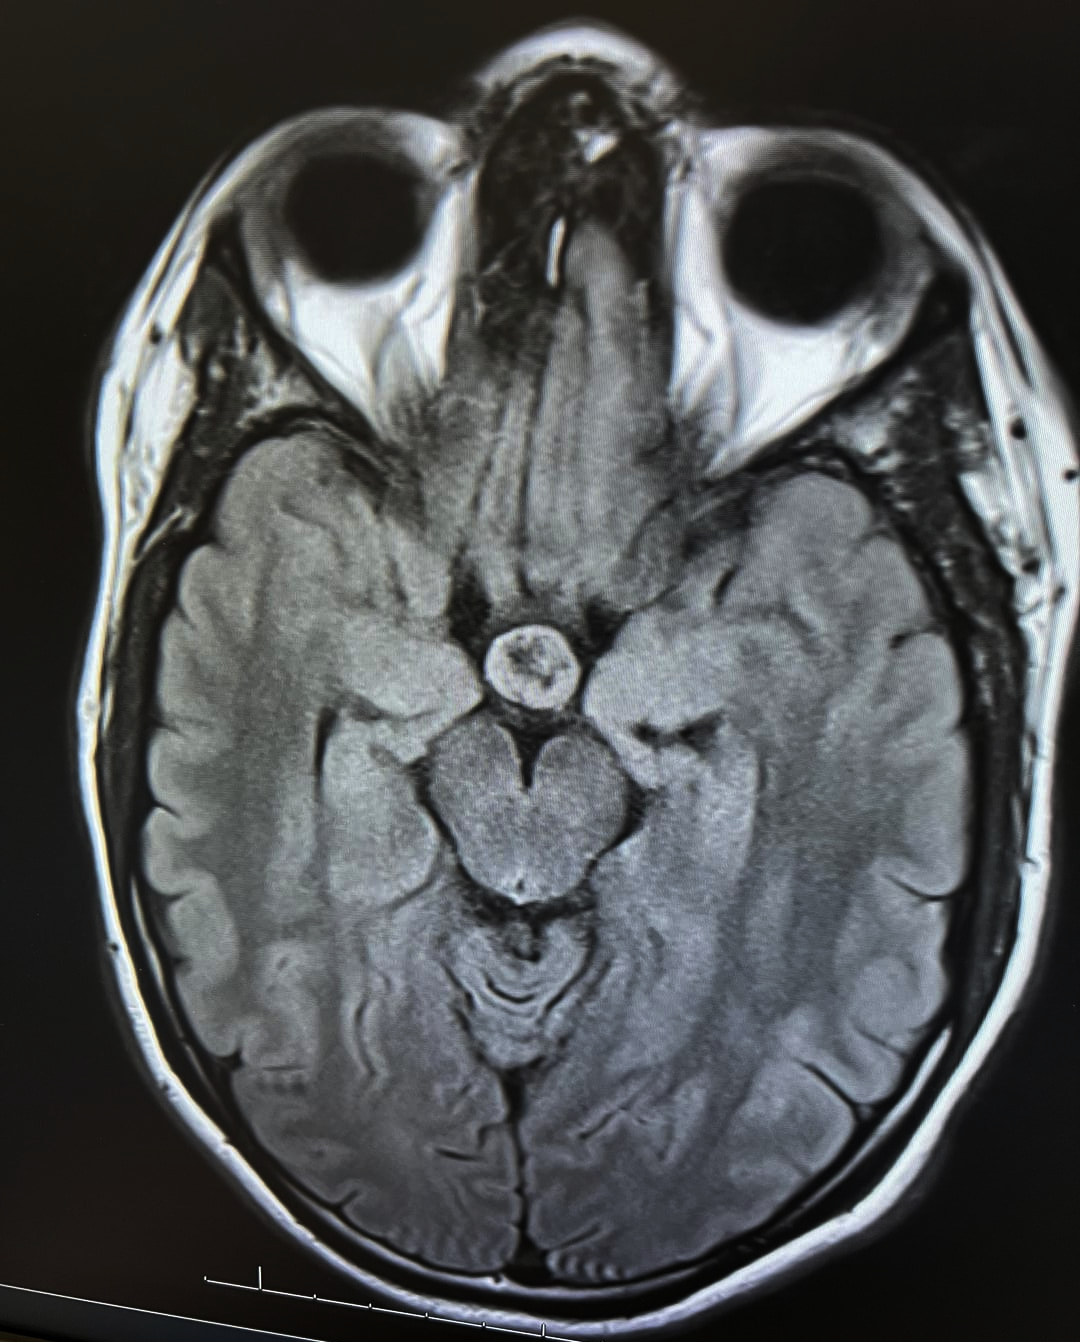

File: IMG_4265.png 📥︎ (1.77 MB, 1080x1342) ImgOps

I just got diagnosed with a brain tumor

It looks like a really deformed slopjak